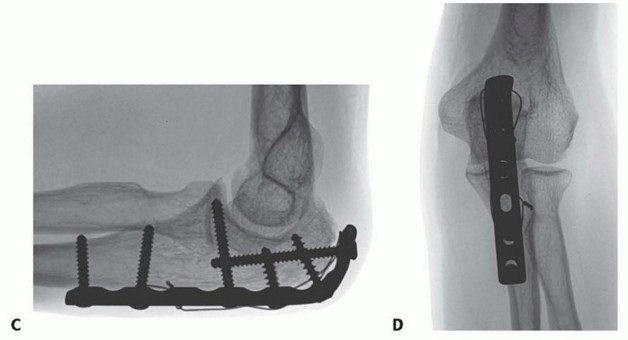

TECH FIG 3 • A. A lateral radiograph illustrates a comminuted olecranon fracture with a small proximal olecranon fragment. B. An oblique view shows the fragmentation. C. A 3.5-mm limited-contact dynamic compression plate and screws contoured to wrap around the dorsal surface of the olecranon is used for fixation. D. A 22-gauge stainless steel wire engages the triceps insertion— this is useful when the olecranon fragment is small, fragmented, or osteopenic. (Copyright , MD.) Distally, a dorsal plate will lie directly on the apex of the ulnar diaphysis. The muscle need only be split sufficiently to gain access to this apex—there is no need to elevate the muscle or periosteum off either the medial or lateral flat aspect of the ulna.No attempt is made to precisely realign intervening fragmentation— once the relationship of the coronoid and olecranon facets is restored and the overall alignment is restored, the remaining fragments are bridged, leaving their soft tissue attachments intact.Bone grafts are rarely necessary if the soft tissue attachments are preserved.If the olecranon fragment is small, osteoporotic, or fragmented, a wire engaging the triceps insertion should be used to reinforce the fixation ( TECH FIG 3D).The plate and screws will serve to hold the coronoid and olecranon facets in proper alignment and bridge fragmentation, and the wire will help ensure fixation even if screw purchase is lost.P.1913. Plate and Screw Fixation of the Fracture-Dislocations of the Olecranon

TECH FIG 5 • A. When there is diaphyseal comminution, a temporary external fixator may be useful. B. A long, 3.5-mm limited contact dynamic compression plate is used for fixation. A 22-gauge stainless steel wire is used to enhance fixation of the comminuted olecranon fragments. C. The comminution extending into the diaphysis heals with the bridging plate. The trochlear notch is restored with good elbow function. (B,C: Copyright , MD.)